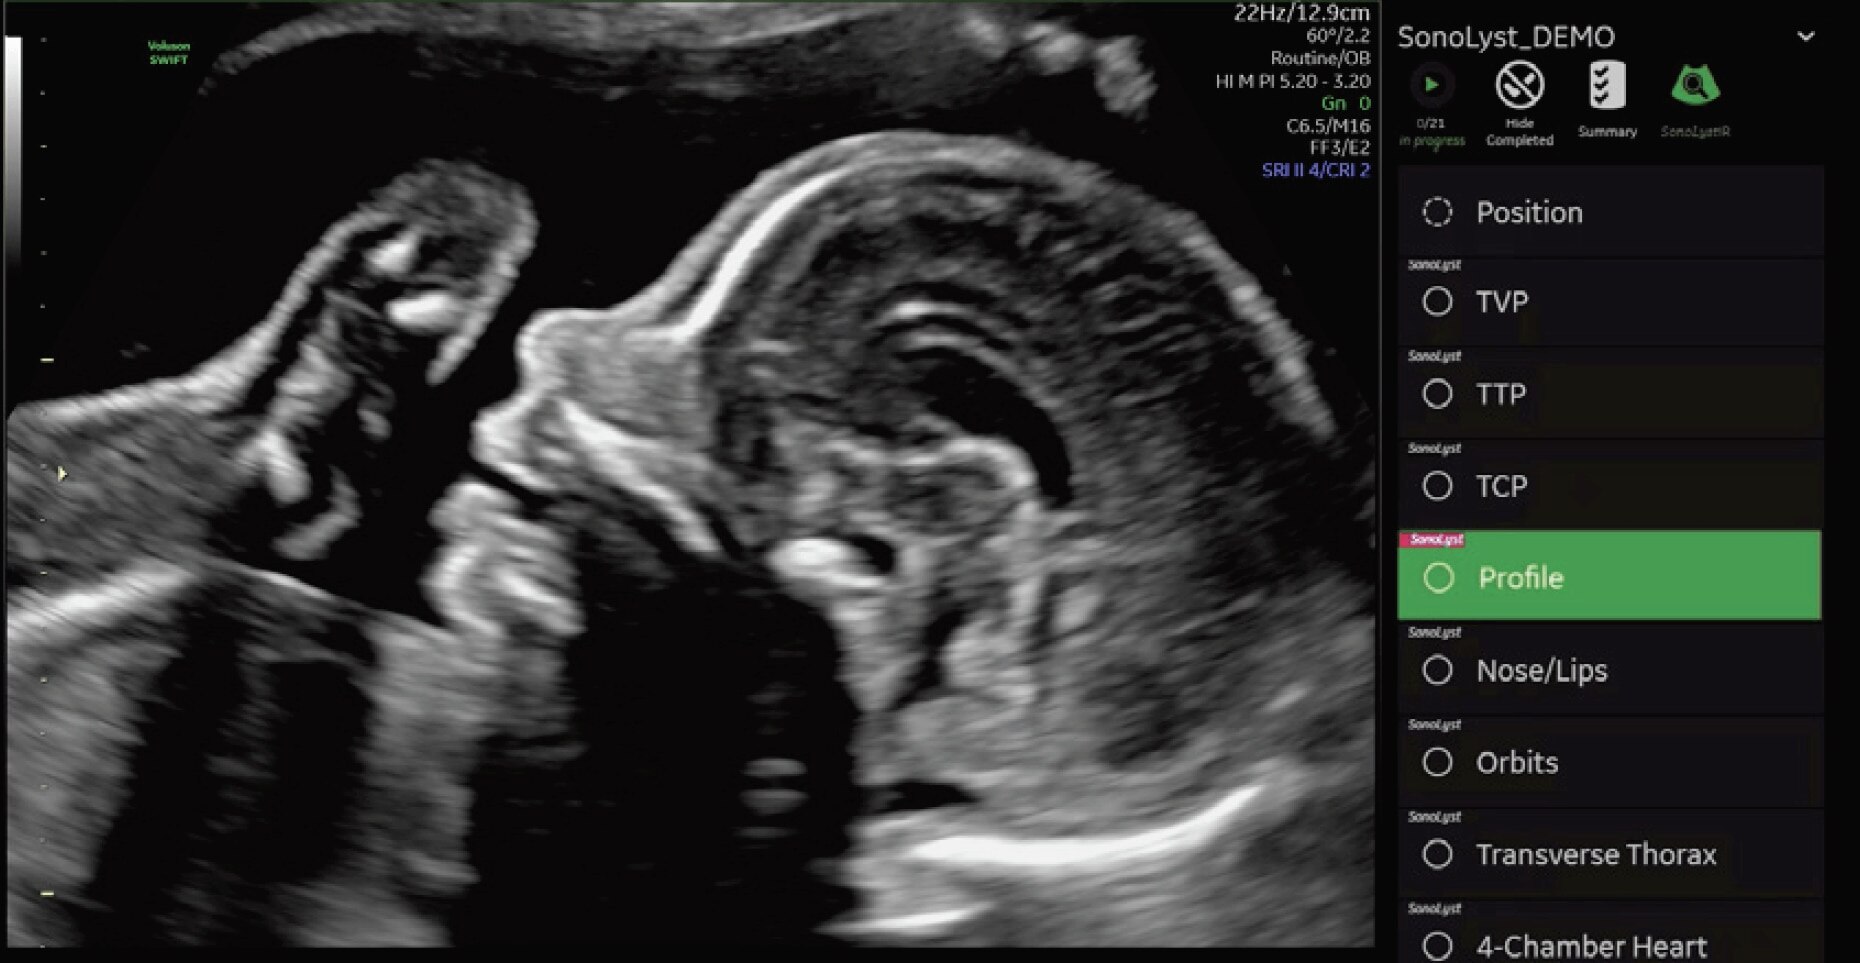

• SonoLystlive: No freezing, no annotating, no storing. SonoLystlive takes image recognition to the next level by capturing images as you scan, in real-time.